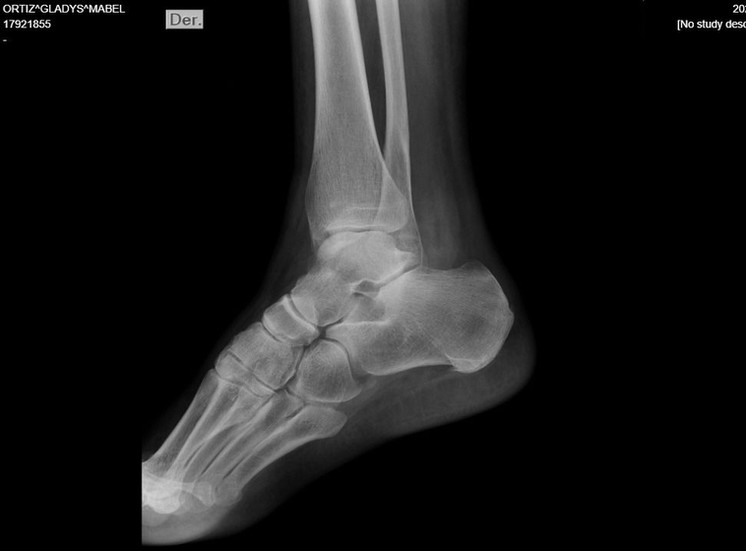

El golpe le provocó fractura de peroné y esguince de tobillo, lesiones que derivaron en una prescripción médica de 30 días de reposo y la imposibilidad de asistir a su trabajo. “Gracias a Dios mi nieta no se hizo nada”, agregó.